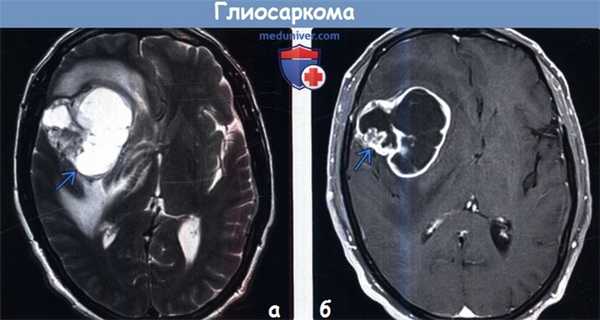

(а) МРТ, Т2-ВИ, аксиальный срез: у мужчины 57 лет в правой лобной доле определяется гетерогенное объемное образование.

(б) МРТ, постконтрастное Т1 -ВИ, режим подавления сигнала от жира, аксиальный срез: у того же пациента определяется неоднородный ободок контрастирования вокруг центральной области понижения сигнала вследствие некроза. При отсутствии вовлечения твердой мозговой оболочки глиосаркома неотличима от типичной МГБ.

Обе эти опухоли IV степени злокачественности по классификации ВОЗ (grade IV) объединяет неблагоприятный прогноз.